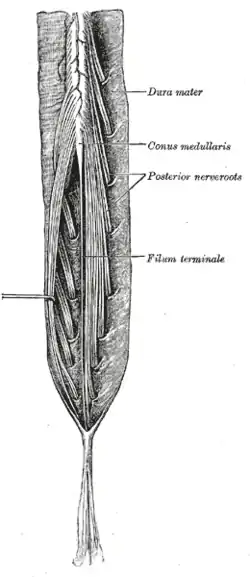

| The cauda equina is the "horse tail" of nerves that branch off after the conus medullaris | |

After the conus medullaris (near lumbar vertebral levels 1 (L1) and 2 (L2), occasionally lower), the spinal canal contains a bundle of nerve fibers (the cauda equina or "horse-tail") that branches off the lower end of the spinal cord and contains the nerve roots from L1–L5 and S1–S5. The nerve roots from L4–S4 join in the sacral plexus which affects the sciatic nerve, which travels caudally (toward the feet). Compression, trauma or other damage to this region of the spinal canal can result in cauda equina syndrome.